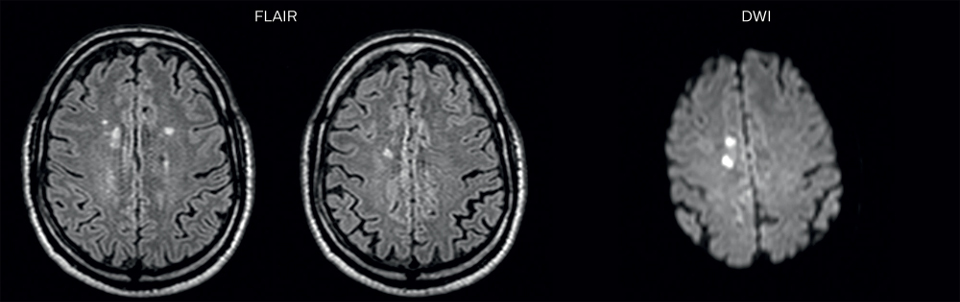

On FLAIR images we can see some nonspecific high signal abnormalities in frontal white matter bilaterally. On DWI we can see acute ischemic lesions which appear with high signal intensity. Arrows show vessel wall enhancement which appears concentric and homogeneous in different cerebral territories.

Arrows show vessel wall enhancement which appears concentric and homogeneous in different cerebral territories.

On the routine MR sequences that we did, we could see acute ischemic lesions. We see them very well on the diffusion images, where acute ischemic lesions usually appear with high signal intensity and restricted diffusion. However, the etiology of these lesions cannot be derived from these images. An area of restricted diffusion was seen in the anterior cerebral artery territory and we concluded it was an ischemic lesion. On MR angiography we can just see if there is stenosis or vessel occlusion, but it does not provide us information on the etiology of this kind of lesion. So, we decided to perform Black Blood imaging. The presence and the pattern of vessel wall enhancement on Black Blood imaging, can help us to determine the etiology of the lesion. differentiate vasculitis from other causes of vasculopathy, such as atherosclerosis, with a high specificity [1-3]. In an atherosclerotic lesion, vessel wall thickening and enhancement are usually eccentric, while in vasculitis the wall thickening and enhancement are usually concentric, homogenous, and in a long portion of the vessel. of patients whenever their treatment is installed in order to determine the efficacy of a particular treatment. In this case the Black Blood imaging helped us to suggest the diagnosis of HIV-related brain vasculitis.